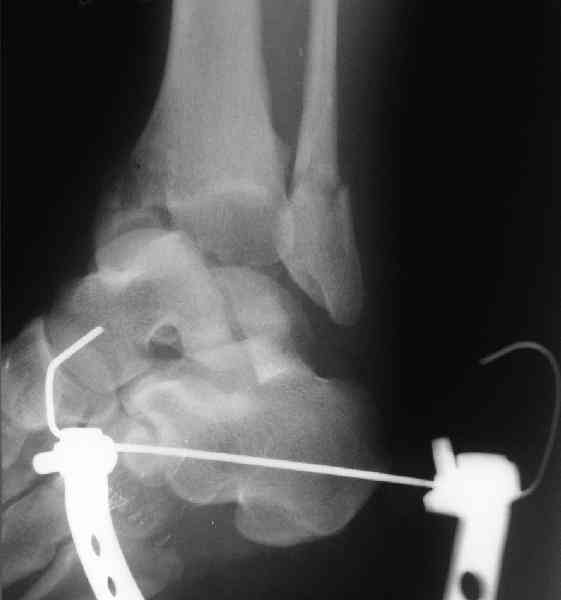

Re: повреждение таранной кости

повторили рентгенограммы и доделали проекции, к единому мнению все еще не пришли